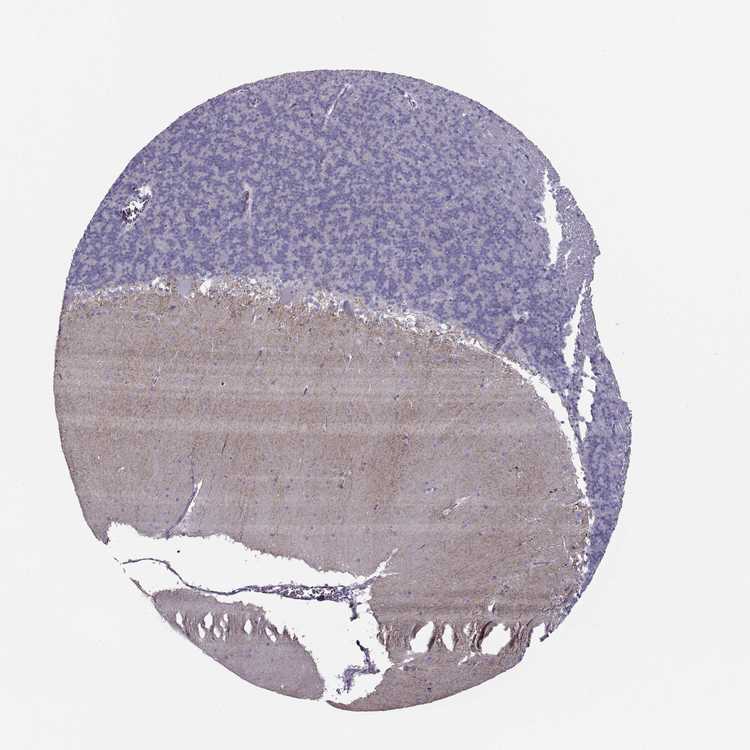

BRAIN CEREBELLUM Show tissue menu

CEREBELLUM - Antibody stainingi

Antibody staining in the annotated cell types in the current human tissue is reported as not detected, low, medium, or high, based on conventional immunohistochemistry profiling in selected tissues. This score is based on the combination of the staining intensity and fraction of stained cells.

Each image is clickable and will lead to virtual microscopy that enables deeper exploration of all samples and also displays staining intensity scores, fraction scores and subcellular localization as well as patient and tissue information for each sample.

Antibody HPA077685

Purkinje cells Not detected

Cells in granular layer Not detected

Cells in molecular layer Low